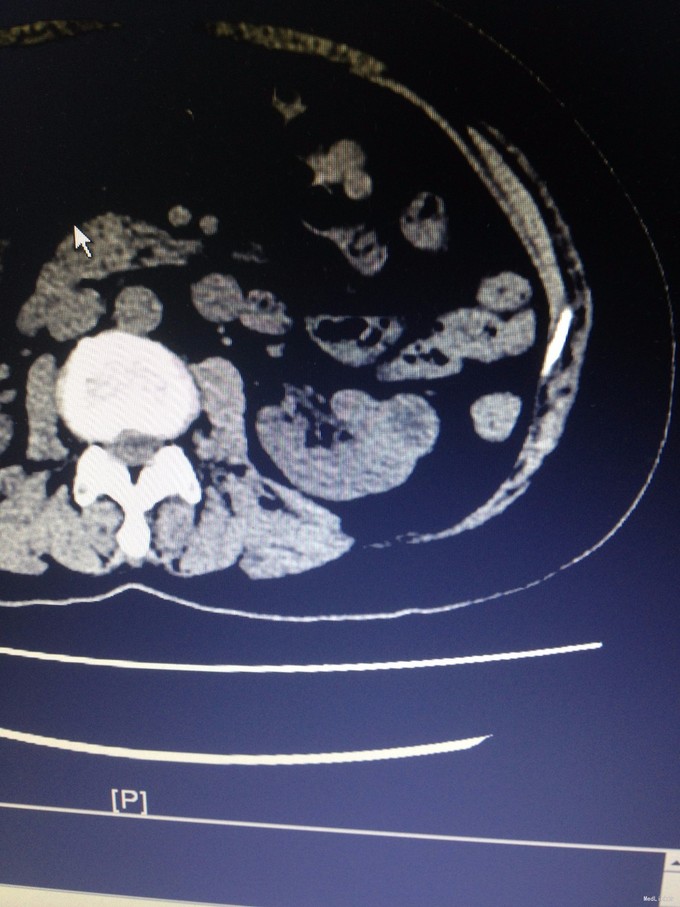

主诉:左腰部隐痛1月余 病史:患者老年女性, 61岁,1月余前无明显诱因出现左腰部隐痛,伴轻微酸胀感,无其他不适,未予就诊。1周前突发头晕、头胀痛感,至当地医院测血压得180/110mmhg。行腹部CT检查提示:左肾占位,肾癌可能性大。脂肪肝,腹主动脉钙化灶。予降压药物治疗后血压得以控制。现为进一步诊治收入我科。既往高血压病史5年,规律服药,血压控制良好。母亲因牙髓癌去世。

查体:腹部平软,无压痛反跳痛,双肾区无叩痛。 辅查:腹部CT提示:左肾占位,肾癌可能性大。脂肪肝,腹主动脉钙化灶。

诊断:左肾癌 治疗:完善术前准备后,行腹腔镜下左肾部分切除术,术程顺利,术后恢复良好。病理结果未回报。